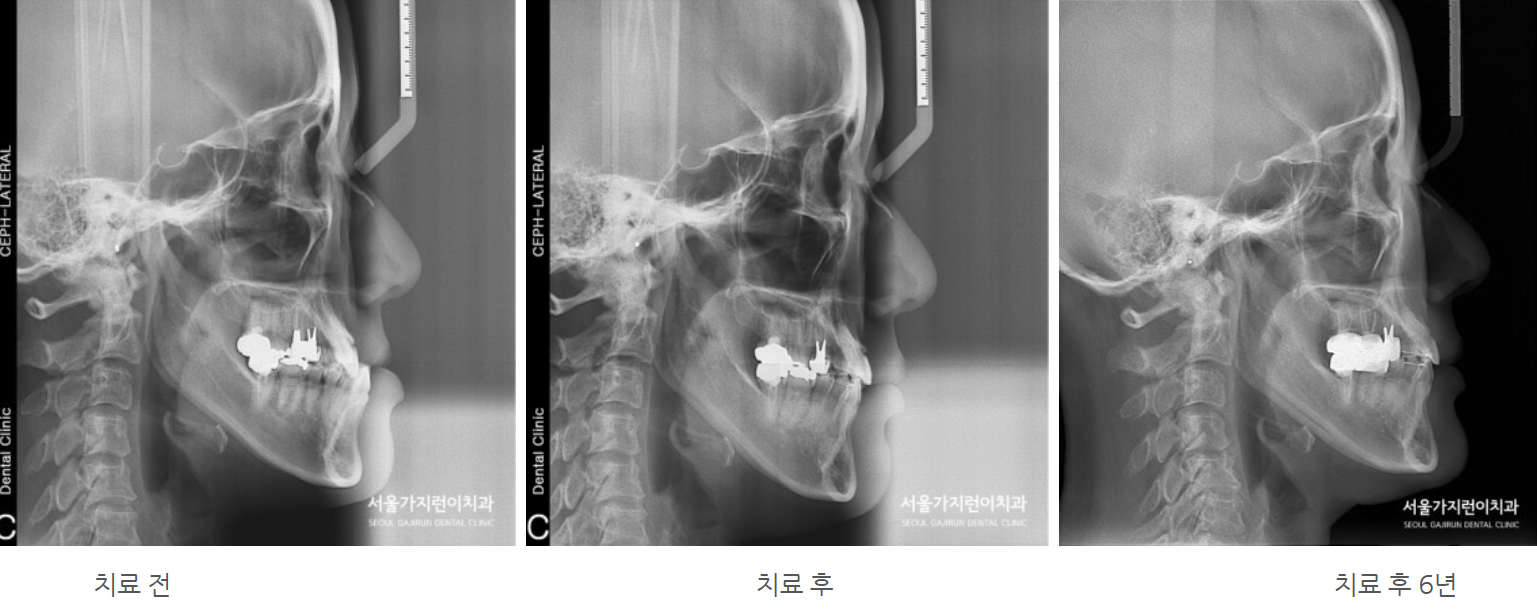

환자분의 경우 주걱턱교정이 시급한 경우였는데요. 주걱턱으로 인해 퉁명스러워 보이는 이미지를 갖고 있어서 외모적으로도 상당한 고민을 갖고 있었던 사례였습니다. 특히 하악골이 왼쪽으로 치우쳐진 비대칭도 있었기 때문에 교합 상태가 좋지 않았는데요.

그래서 서울가지런이치과 교정과 의원에서는 치아를 발치한 후에 상하악 치아배열을 바로 잡기로 했는데요. 어금니 교합을 정상으로 만들기 위해서는 상당히 많은 치아 이동이 필요한 상태였습니다. 치아이동에 사용된 장치로는 전방 이동을 위한 미니스크류와 레버암이 있는데요. 치아를 이동시키면서 다른 치아가 움직이지 않도록 지지대 역할도 하면서 충분한 이동에 도움이 될 수 있도록 레버암까지 동원해 힘의 작용방향과 크기를 조절하였습니다.

주걱턱도 개선해야 했지만 정상교합으로 돌려놓기가 쉽지 않았는데요. 환자분의 경우 치료 1년 후 안정적으로 교정치료를 마쳤으며 6년이 지난 지금까지 안정적인 상태를 유지하고 있었습니다. 이 사진을 보면 교정이 잘 이루어져 재발하지 않았다는 것을 확인할 수 있는데요.